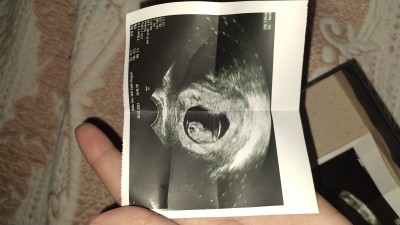

Kızlar keseden cinsiyet belli oluyor diye duymuştum yapanlar varmış anlayanlar yapabilir mi teşekkür ederim bir de 7+6 iken ultrasyon da 8+2 göründük böyle oynama olabiliyor mu ? Cevaplarınız için şimdiden teşekkürler <3

Gebelik haftası 8